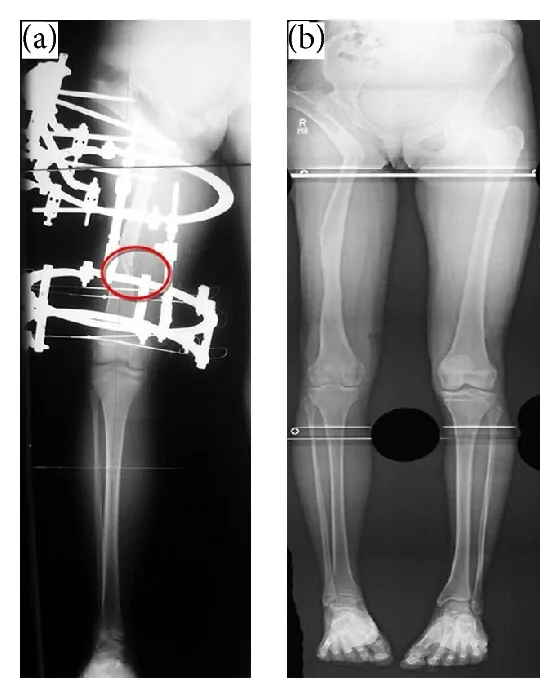

Osteotomy means making a controlled cut in the bone to allow correction. In Ilizarov Hip Reconstruction, the surgeon carefully cuts the femur or pelvis so the external fixator can gradually realign the hip. This process allows bone healing while correcting deformities or leg length differences.

The Ilizarov technique uses a circular external fixator that applies gentle, controlled tension to bones. This stimulates natural bone regeneration (distraction osteogenesis), which allows bones to grow in length and correct deformities. It is widely used for hip, leg, and complex orthopedic reconstructions.